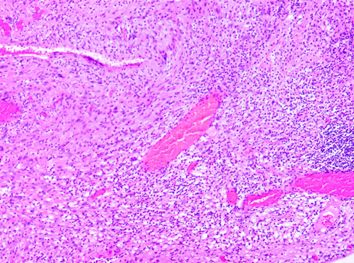

患者入院后进一步行腰椎增强磁共振检查,提示:腰1/2椎体水平椎管内膜内髓外占位,大小约14mm*15mm*22mm(左右*前后*上下),考虑神经鞘瘤(图1)。

图1. 腰椎增强磁共振:A. T2加权,混杂高信号。B.增强扫描,肿块呈不均匀强化,提示病灶内囊变。